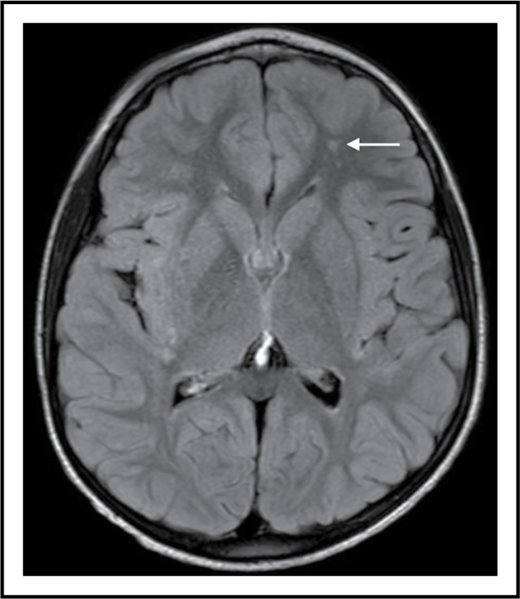

SCI is a supply-side problem in sickle cell anemia. The arrow shows a small stroke by magnetic resonance imaging (MRI) that has no corresponding deficit on physical examination (ie, SCI) in the left frontal white matter in a 6-year-old child with sickle cell anemia.

SCI is the term for a subset of strokes, usually small, that have no localizing signs. However, it should not be reassuring that the physical examination of an individual with SCI is normal, because the brain is composed of more than motor and somatosensory cortex and associated long tracts. These small strokes (see figure) are morbid, not silent, and can limit academic attainment and impair cognition in children and adults with sickle cell anemia.2 Moreover, SCI increases the risk for subsequent overt strokes, even in those who have normal transcranial Doppler (TCD) examinations.2,3